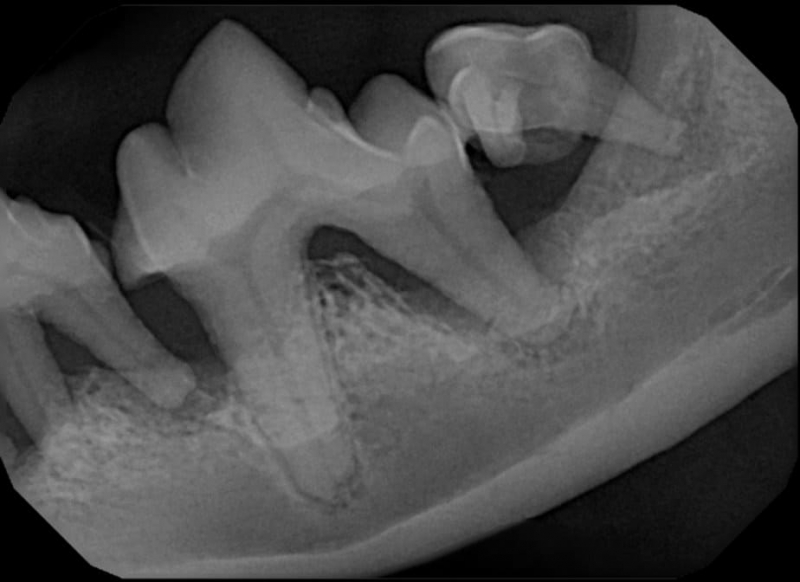

Periodontal disease is extremely common in dogs and cats. Over 80% of dogs and cats over two years of age have some degree of periodontal disease. Periodontal disease is best prevented by yearly professional dental cleanings starting at two years of age and at home brushing at least three times weekly. Brushing should begin at a very early age to allow your new pet to get used to regular brushing. In severe cases of infection or periodontal disease, the teeth may need to be surgically extracted. Extractions should always involve x-rays of the tooth first, as many teeth have multiple roots or may be diseased below where the eye can see. Extracting larger teeth in animals requires oral surgery, equivalent to removing wisdom teeth in people. It is vital that all of the tooth and roots be removed for the periodontal infection to resolve. In cases of important teeth with mild to moderate periodontal disease, multiple periodontal treatments can be offered to help save these teeth.